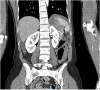

Presentation of case: Our patient is a 35-year-old female who was a restrained front seat passenger in a car vs. tree collision at 80 km/h. Her seat belt was worn with the shoulder strap under her left axilla. She sustained multiple injuries including complete transection of the gastroduodenal junction. In addition to this she had splenic, liver, transverse colonic, left lower rib and humeral injury. She underwent damage control laparotomy with splenectomy; re-look with gastrojejunostomy and transverse colonic resection with defunctioning ileostomy. She made a good recovery and was discharged after a 4 week admission.